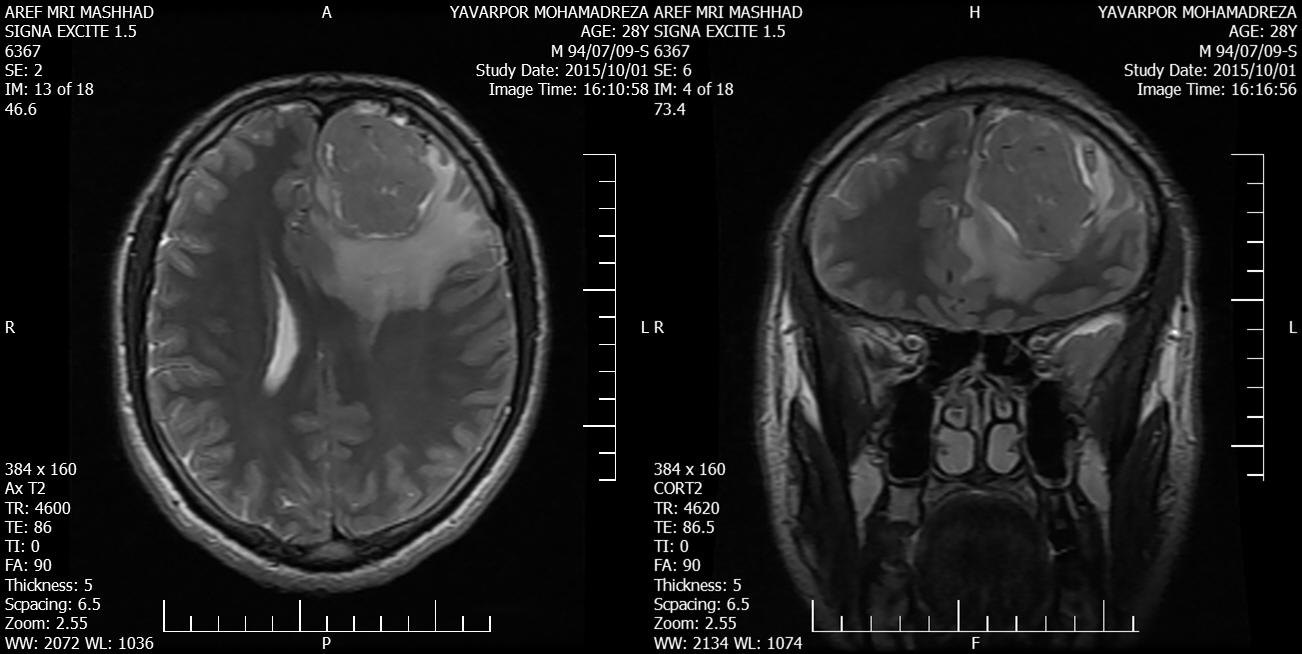

Background: Chondrosarcoma is a very rare brain tumor. Patients with mesenchymal chondrosarcoma have a worse prognosis and survival than other subtypes of brain chondrosarcoma. Case Report: A 29-year-old man underwent craniotomy because of a headache and blurred vision in his left eye lasting for 15 days. Pathologic examination revealed mesenchymal chondrosarcoma. Conclusion: Chondrosarcoma should be considered in the differential diagnoses of intracranial extra-axial hypo- and hypervascular tumors, especially in young patients. Surgical resection and radiotherapy are the preferred treatment for these patients.[GMJ.2016;5(4):219-24]